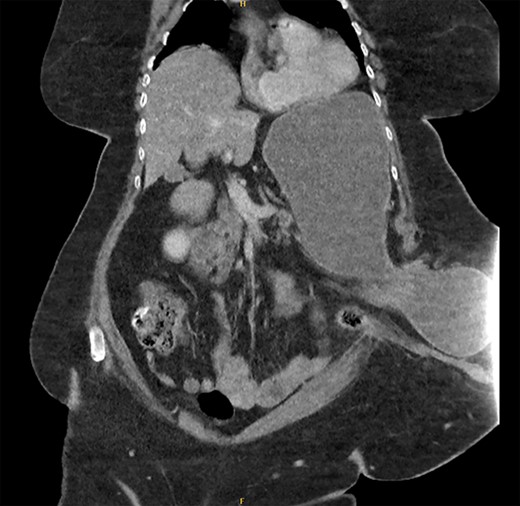

The patient underwent a CT abdomen pelvis (Figs 1 and 2), which reported bowel obstruction secondary to a parastomal hernia on the left containing a large portion of the stomach’s body and antrum.

CT abdomen pelvis—axial view of parastomal hernia containing stomach.